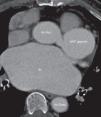

La relación diámetro de aneurisma/diámetro de vaso de referencia osciló entre 1,6-2,4 en 16 de los pacientes diagnosticados de AAC. Analizando la morfología, 14 aneurismas eran saculares (7 con cuello y 7 sin cuello), 5 tenían aneurismas fusiformes (fig. 2). El paciente 17 presentó un aneurisma gigante (45,0×47,0mm) (fig. 3).

Se ha descrito previamente en la literatura el AAC como factor independiente de riesgo de mortalidad10. En relación con los aneurismas gigantes, la cirugía parece ser la terapia más adecuada por el riesgo de rotura, trombosis o vasoespasmo1,2. Sin embargo, no existen en la literatura directrices específicas para este tipo de patologías. Las guías de la Sociedad Americana de Cardiología para el manejo de pacientes adultos con enfermedades cardíacas congénitas18, consideran (con indicación de clase I), que las anomalías que se localizan en el TC, cuando estas se encuentran entre la arteria pulmonar y aorta, se benefician de una intervención quirúrgica. De la misma manera, se considera que los episodios de isquemia miocárdica que se deban a compresión (como podría ser la existencia de una aneurisma gigante adyacente), deberán ser operados para su reparación. Pero, a pesar de esto, no existen indicaciones en las guías de actuación clínica más consultadas en relación con AAC que no sean considerados como gigantes. En nuestro paciente con aneurisma gigante, existía además una disfunción de la prótesis aórtica mecánica (implantada previamente), motivo por el fue intervenido. En la angiografía coronaria previa a la cirugía se observó la presencia de un aneurisma gigante que se encontraba en el TC, entre la arteria pulmonar y la aorta. El día de la intervención se decidió realizar (además del recambio de prótesis aórtica), la apertura y exclusión del saco aneurismático, que estaba en relación directa con el ostium de la coronaria izquierda. Posteriormente se realizó una derivación aorto-coronaria con safena para restituir el flujo sanguíneo a las arterias coronarias, con buena evolución en el postoperatorio. En este caso en concreto, las dimensiones del aneurisma (figs. 2D y 3) ya le hacían subsidiario de corrección quirúrgica por el riesgo de rotura, y por encontrarse entre la arteria pulmonar y la aorta, tal y como recomiendan las guías americanas18. Sin embargo, un aneurisma de estas dimensiones que se encontrase en otra coronaria, tendría, según nuestra opinión, indicación quirúrgica para evitar complicaciones antes descritas, como ya mencionan algunos autores1,2,5,13.